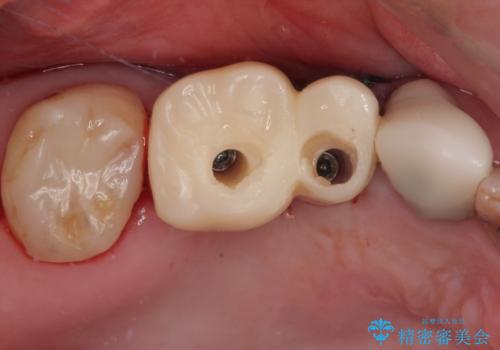

- 欠損や破折により失われた奥歯に、インプラント治療を希望して来院された患者様です。

欠損部はすぐにインプラント埋入が可能で、手前の歯根が残存している部位も、できれば抜歯をして奥と一緒に埋入をしたいところでしたが、破折による炎症が大きいため、2回に分けてインプラント埋入を行うこととしました。